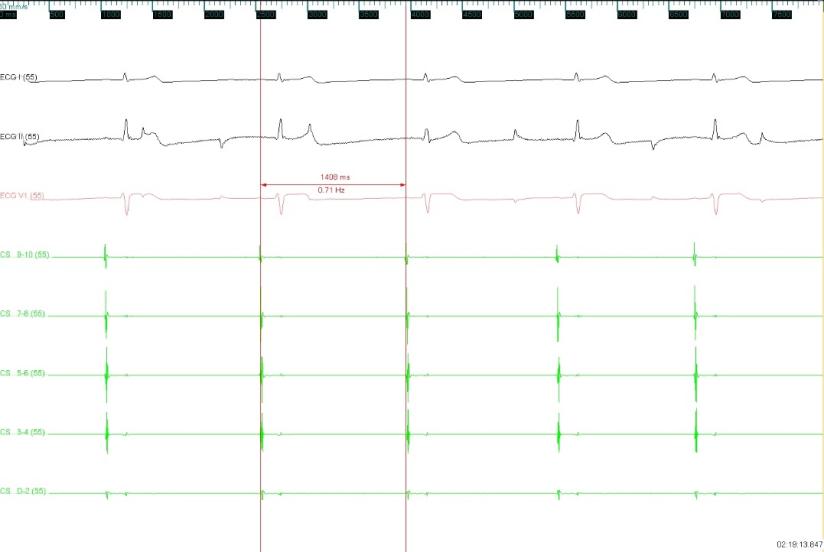

图1 术前心率43次/分

经与患方充分沟通治疗方案后,5月9日,在寿锡凌教授指导下,酉鹏华副主任医师、韩稳琦博士、赵永勇主治医师等为患者局麻下成功行经导管心脏迷走神经节消融改良术。术中先行心脏腔内电生理检查术,消融前测窦房结恢复时间(SNRT):1404ms,房室结文氏点(CSNRT):700ms,依次消融左房左上神经节丛(LSGP)、左房左下神经节丛(LIGP)、左肺静脉间神经节丛(MTGP)、左房右前神经节丛(RAGP)、左房右下神经节丛(RIGP),消融RAGP时窦性心房频率从40-46次/分提升至95-100次/分,但表现为房室传导阻滞,房室非1:1传导特点,心室率提升不明显,消融RIGP时房室结迷走张力减低,房室传导明显改善,房室呈1:1传导,心室频率提升至95-100次/分。